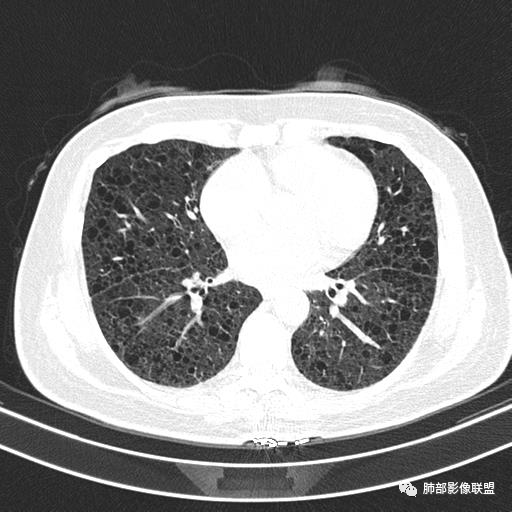

中年女性,不吸烟

双肺弥漫囊腔,累及肋膈角,囊腔形态相对规则单一。

CT平扫示双肺弥漫分布大小不等囊状薄壁透光区,无内、中、外带分布差异,间质稍示增厚。拟LAM

中年女性育龄期妇女,咳嗽气喘,无吸烟史,有苯吸入史。影像:双肺弥漫均匀小囊腔,无明显分布优势,囊腔形态欠规则,壁薄,部分囊腔边缘血管征,伴双肺弥漫磨玻璃影,无结节,考虑lam,鉴别苯中毒肺损伤,囊腔多有分布优势,小叶中心分布为主,形态规整等

中年育龄期女性,双肺多发含气囊腔弥漫性分布,囊间肺组织结构正常,常规考虑Lam

双肺弥漫大小不一薄壁含气囊腔,囊间肺组织正常,正常肺背景,肺尖肺底受累;青年女性,气喘,支持LAM

CT表现:双肺弥漫大小不等的薄壁囊腔,囊壁<2mm,外形规则,血管影多位于囊腔周围,囊腔之间肺组织正常,随着疾病进展到晚期,囊腔变大、增多,不可胜数,囊腔可融合成较大的囊,与肺气肿相似,形成间质性肺纤维化。部分病例可出现结节影。